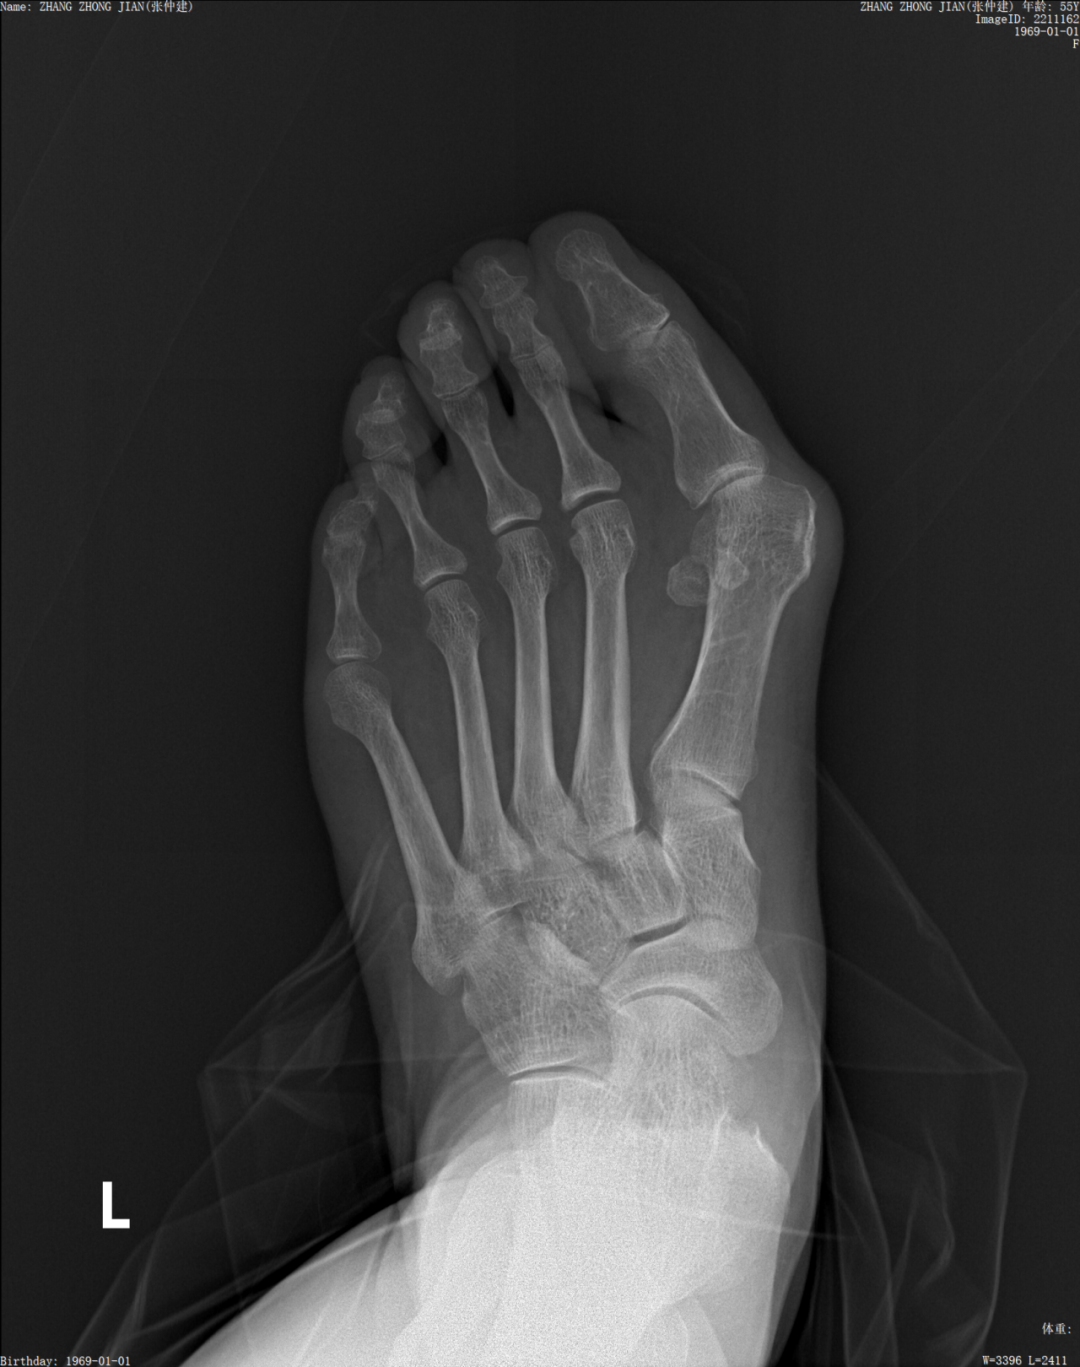

近日,合江县人民医院骨关节外科收治了一名被拇外翻困扰了50多年的患者张阿姨,最近一年,张阿姨的脚出现突起处红肿,疼痛明显,甚至影响了行走,关节外科给她进行了切口不到2厘米的微创手术,术后非常满意地出院了。张阿姨表示:她一直怕治疗效果不好,但又实在很痛,只想做一只脚来看看效果,没想到效果那么好,在做完左脚后立马要求医生做右脚!那么我们就来摆哈拇外翻的龙门阵!

术前